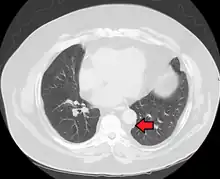

| Mediastinal lipomatosis | |